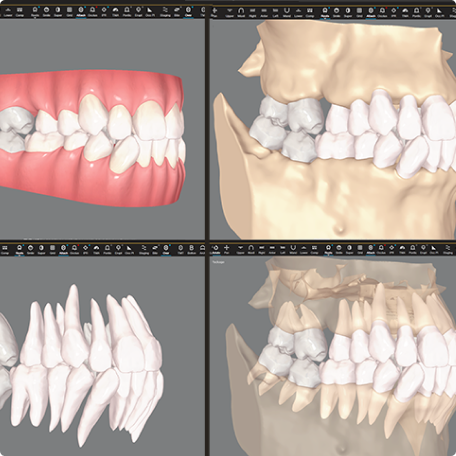

CBCT 연동 시스템: CBCT 데이터를 활용해 잇몸뼈 속 치아 뿌리(치근)의 형태와 위치를 3차원으로 파악합니다. 뿌리의 이동 경로까지 미리 계산하여 더욱 안전하고 정교한 치료 계획을 세웁니다.

고정밀 구강 스캐너: 마이크론 단위까지 잡아내는 최신 스캐너를 통해 환자분의 구강 구조를 오차 없이 재현하며, 이는 곧 장치의 완벽한 밀착력과 효과로 이어집니다.

눈에 보이는 치아 머리(치관)뿐 아니라 이제 치아 뿌리(치근)까지 확인이 가능하고 시뮬레이션이 가능해졌습니다.